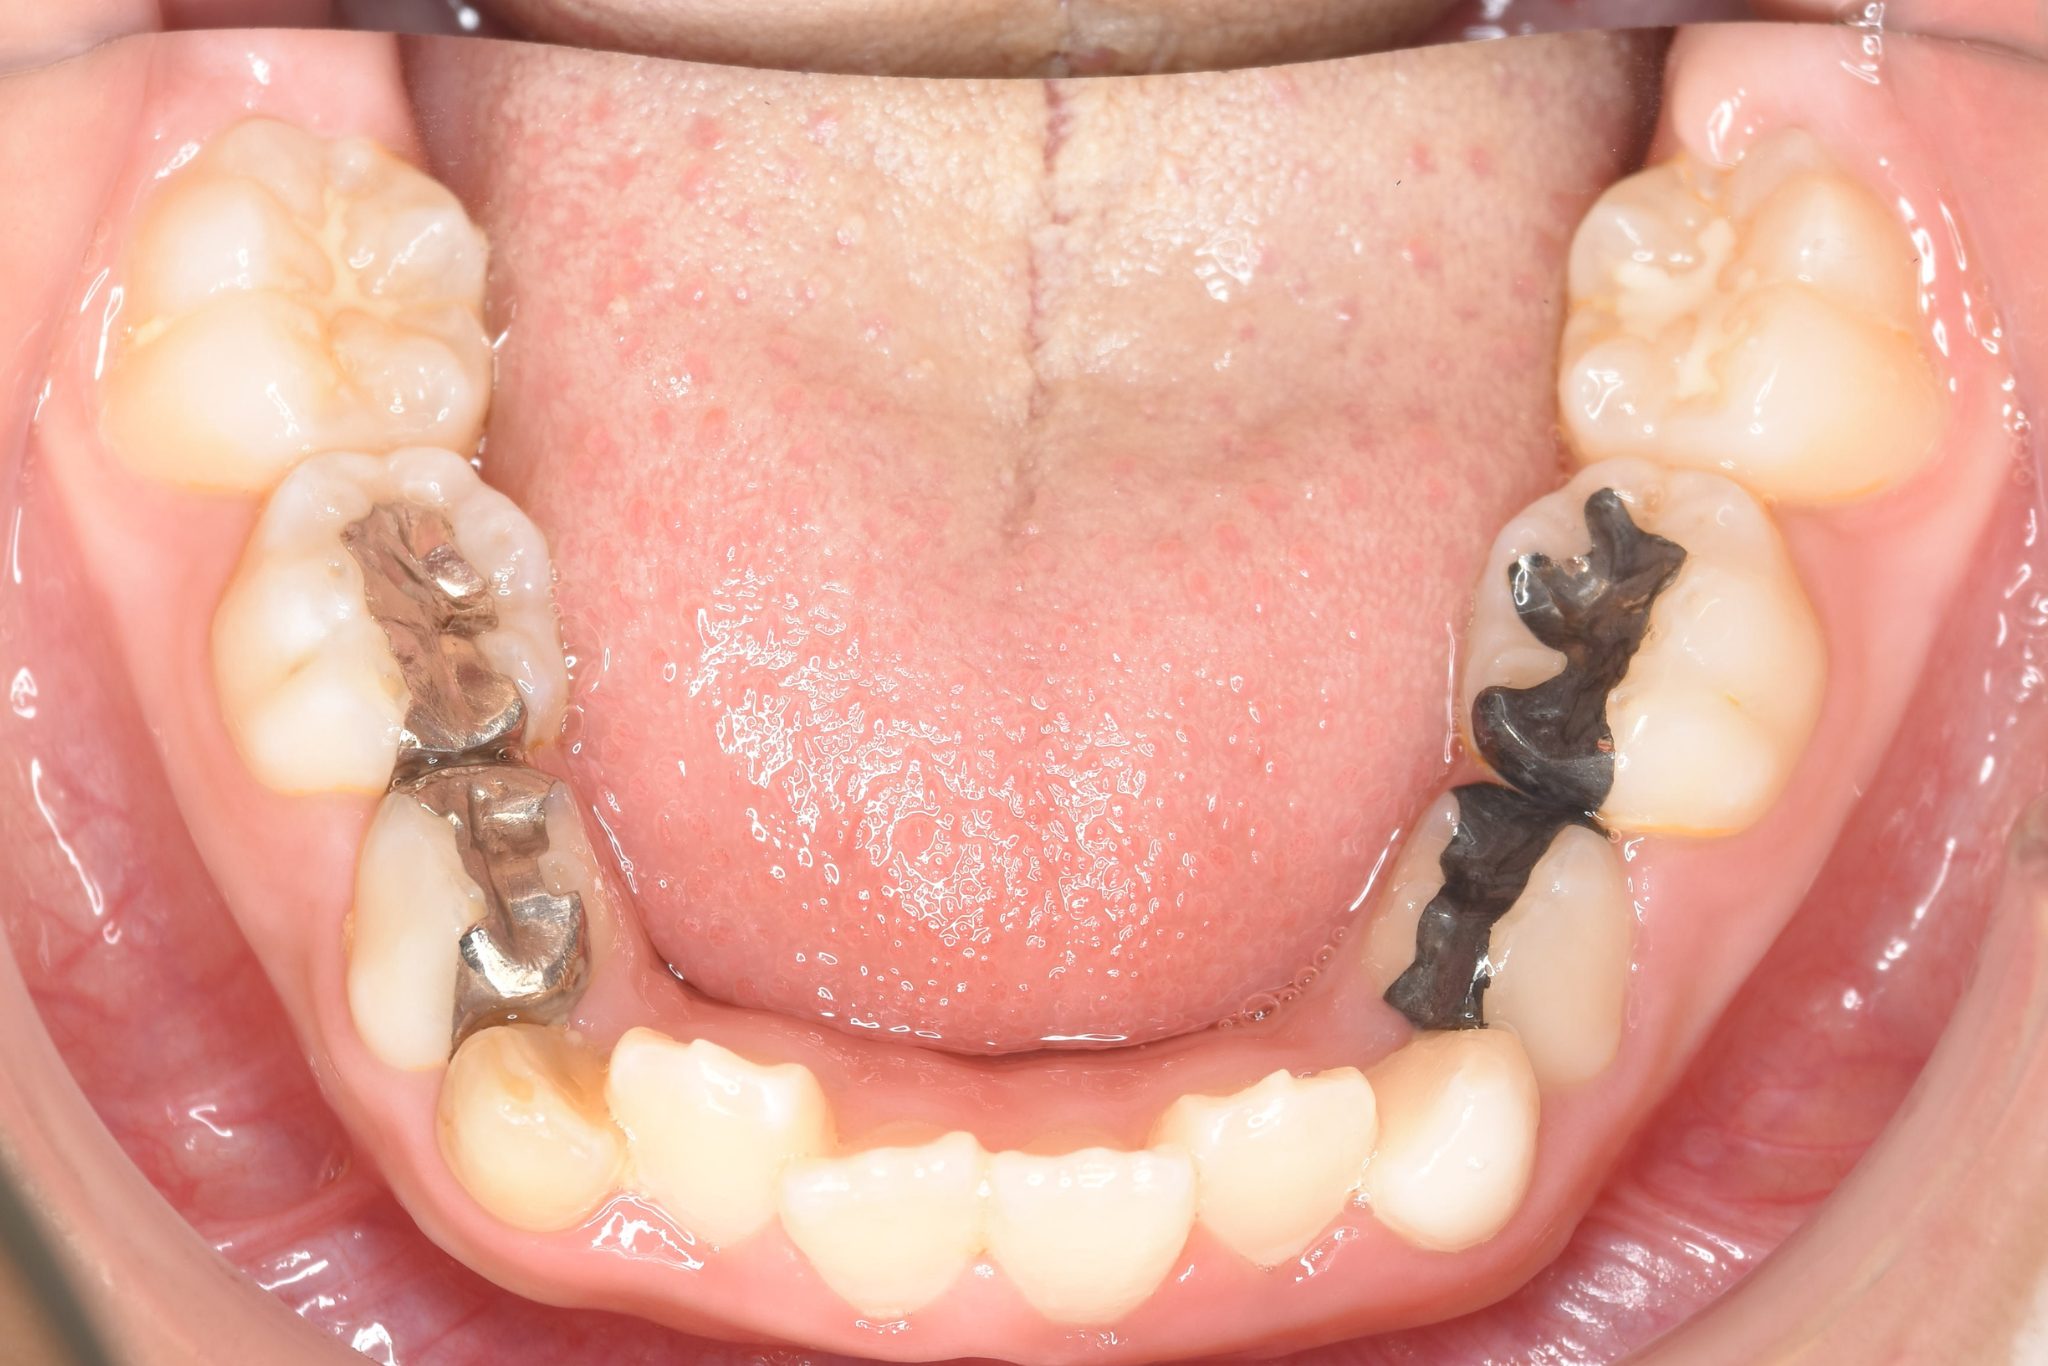

ビフォー

子どもの矯正治療|症例_169

主訴 歯並び|嚙み合わせ|口呼吸

施術内容 上顎急速拡大装置と下顎リンガルアーチを用いて上下顎骨を拡大した。

その後マウスピース型矯正装置で歯牙を配列し良好な咬合を獲得した。